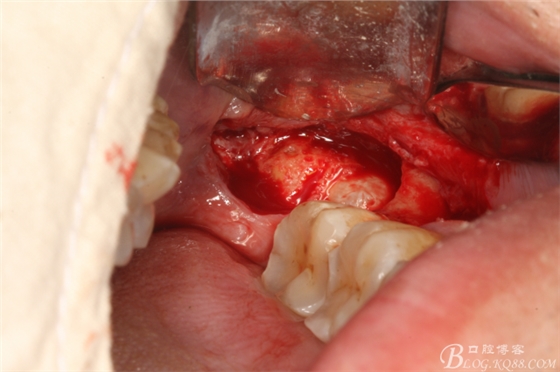

圖三、完全暴露38牙根和牙冠

圖4.橫斷牙根和牙冠